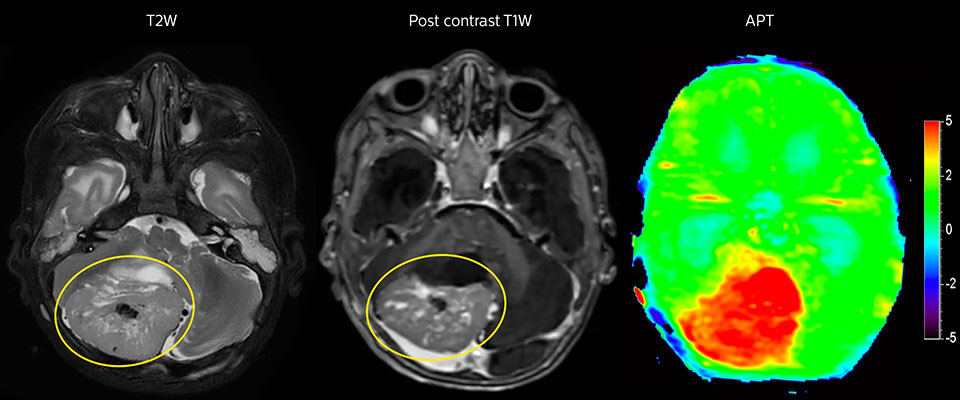

APT imaging of high-grade tumor

Tumor evaluation in a 1-year-old child with medulloblastoma. This aggressive tumor type is very solid and homogeneous. The high APT signal corresponds with the post-contrast image of this high-grade tumor.